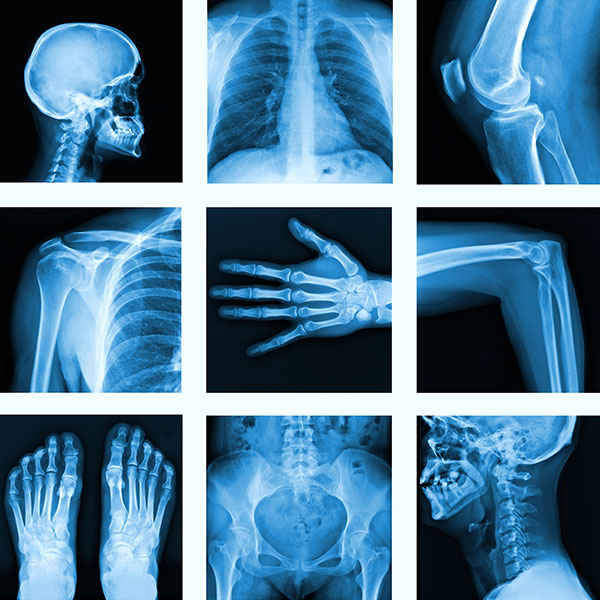

Radiology Technology